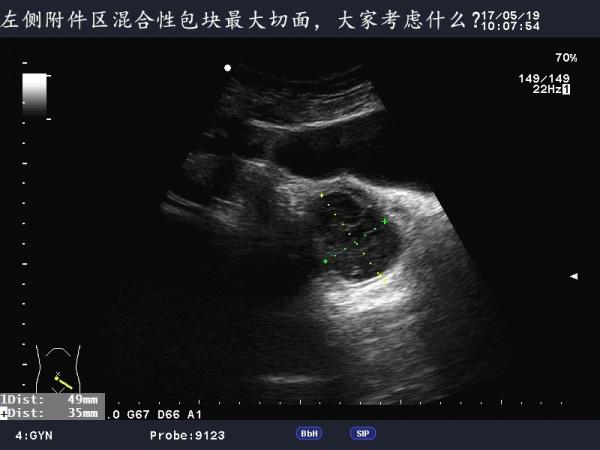

这是巧克力囊肿吗?

患者女,40Y,因下腹部疼痛就诊,最近一次月经来潮量少且疼痛厉害,以往基本上正常。

于月经第11天行B超检查。

不是很典型的巧克力囊肿,可以随访复查看看

可定期复查,黄体不除外